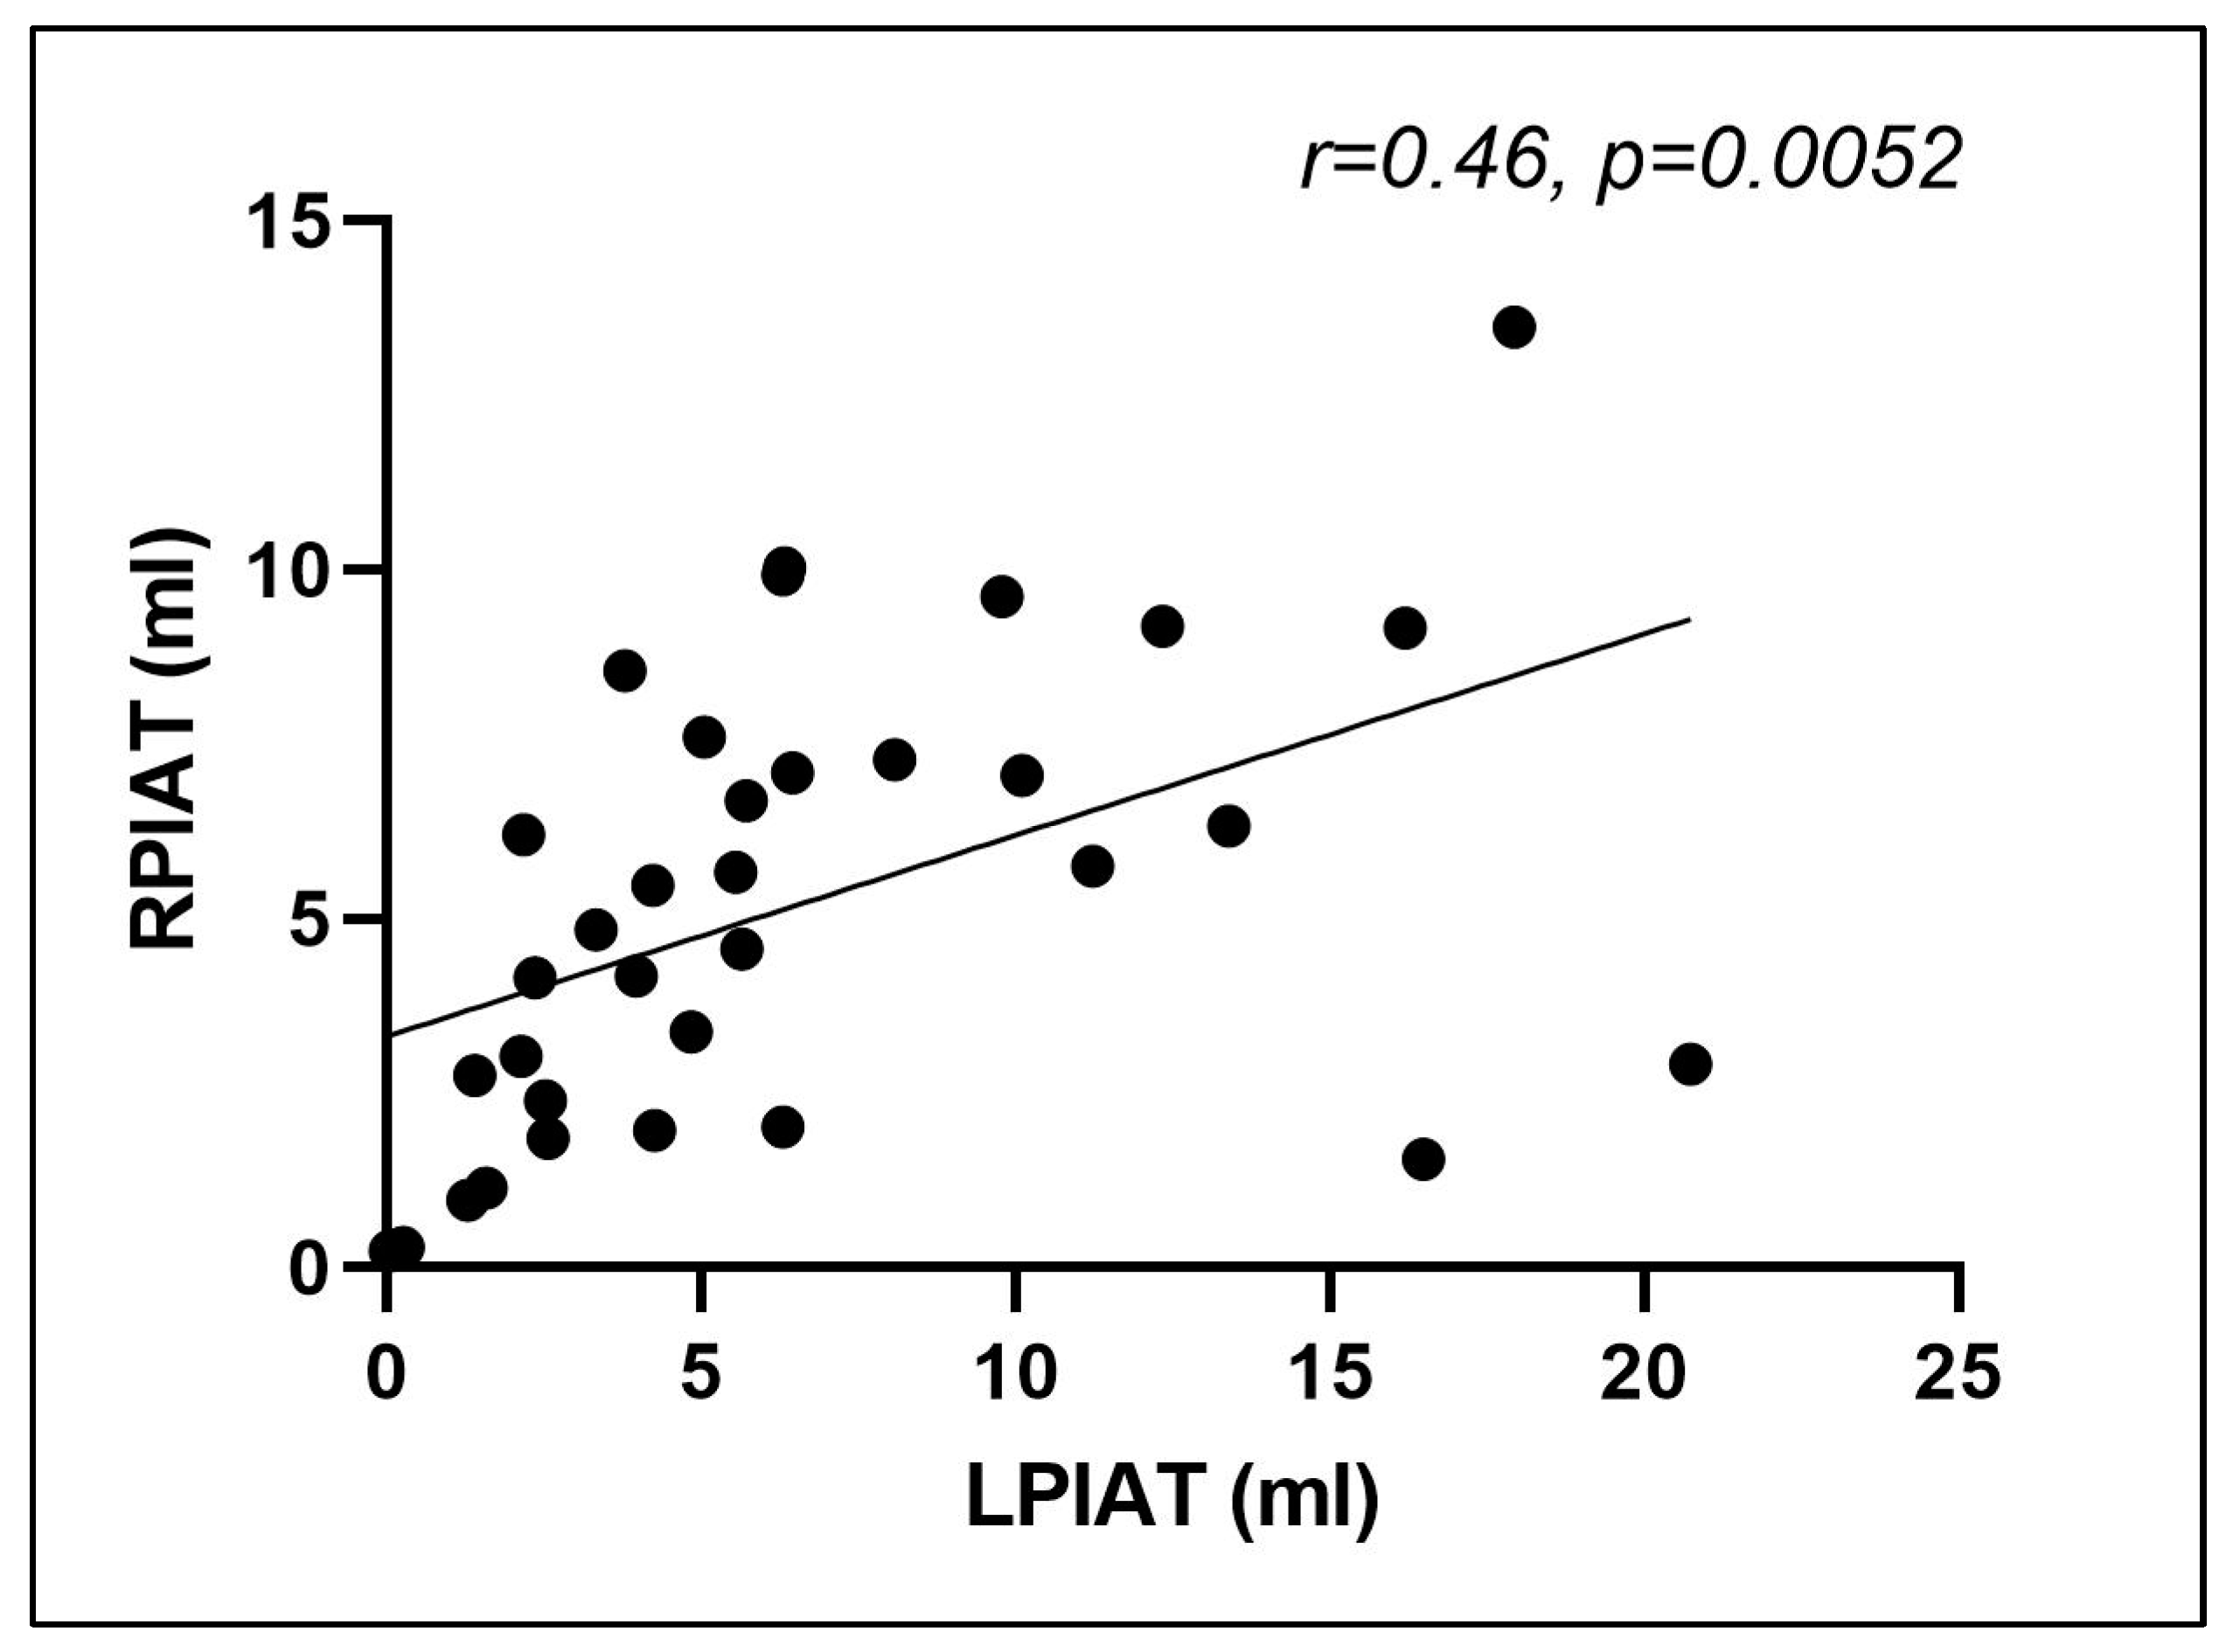

3.3. Computer-Aided Imaging Biomarkers Characterizing Adipose Tissue Distribution